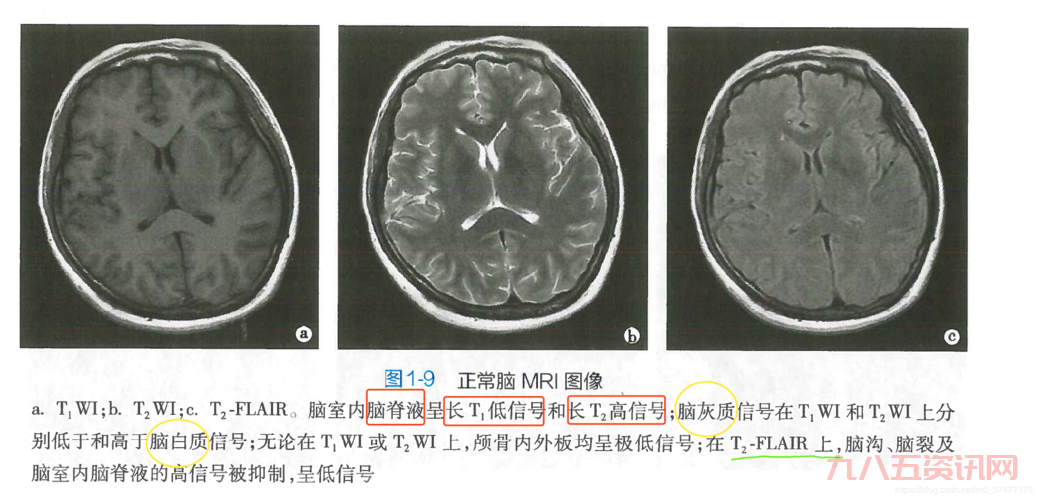

那天,我照常在家搞我的設備,突然就琢磨起這個“t2”到底是个起初我也不懂,就到處找資料,問人,可算是把“t2”是個啥弄明白。這玩意兒在醫學上還是核磁共振成像裡頭的一個關鍵指標,主要说的就是那個橫向磁化矢量恢復到一個平衡時狀態的時間,大概是這個意思。

- 像那個頸椎T2,說的就是在做核磁共振的時候,那個橫向磁化矢量衰減到最大值的百分之37所需要的時間。

- 還有那個T2信號影,就是說在核磁共振成像裡頭,組織在T2加權圖像上的表現。